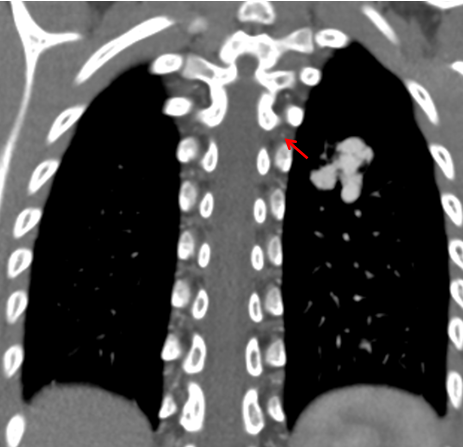

6歲的夕夕(化名)在查體時(shí)發(fā)現(xiàn)了肺上長(zhǎng)了一團(tuán)迂曲增粗的異常血管影。雖然孩子除了活動(dòng)耐力略差外,其他方面看起來(lái)一切正常,出于謹(jǐn)慎考慮,夕夕媽媽還是帶著孩子來(lái)到了青島婦兒醫(yī)院。血管瘤&脈管畸形專(zhuān)科醫(yī)師接診后對(duì)孩子進(jìn)行了相關(guān)檢查,診斷夕夕患有“肺動(dòng)靜脈瘺”!